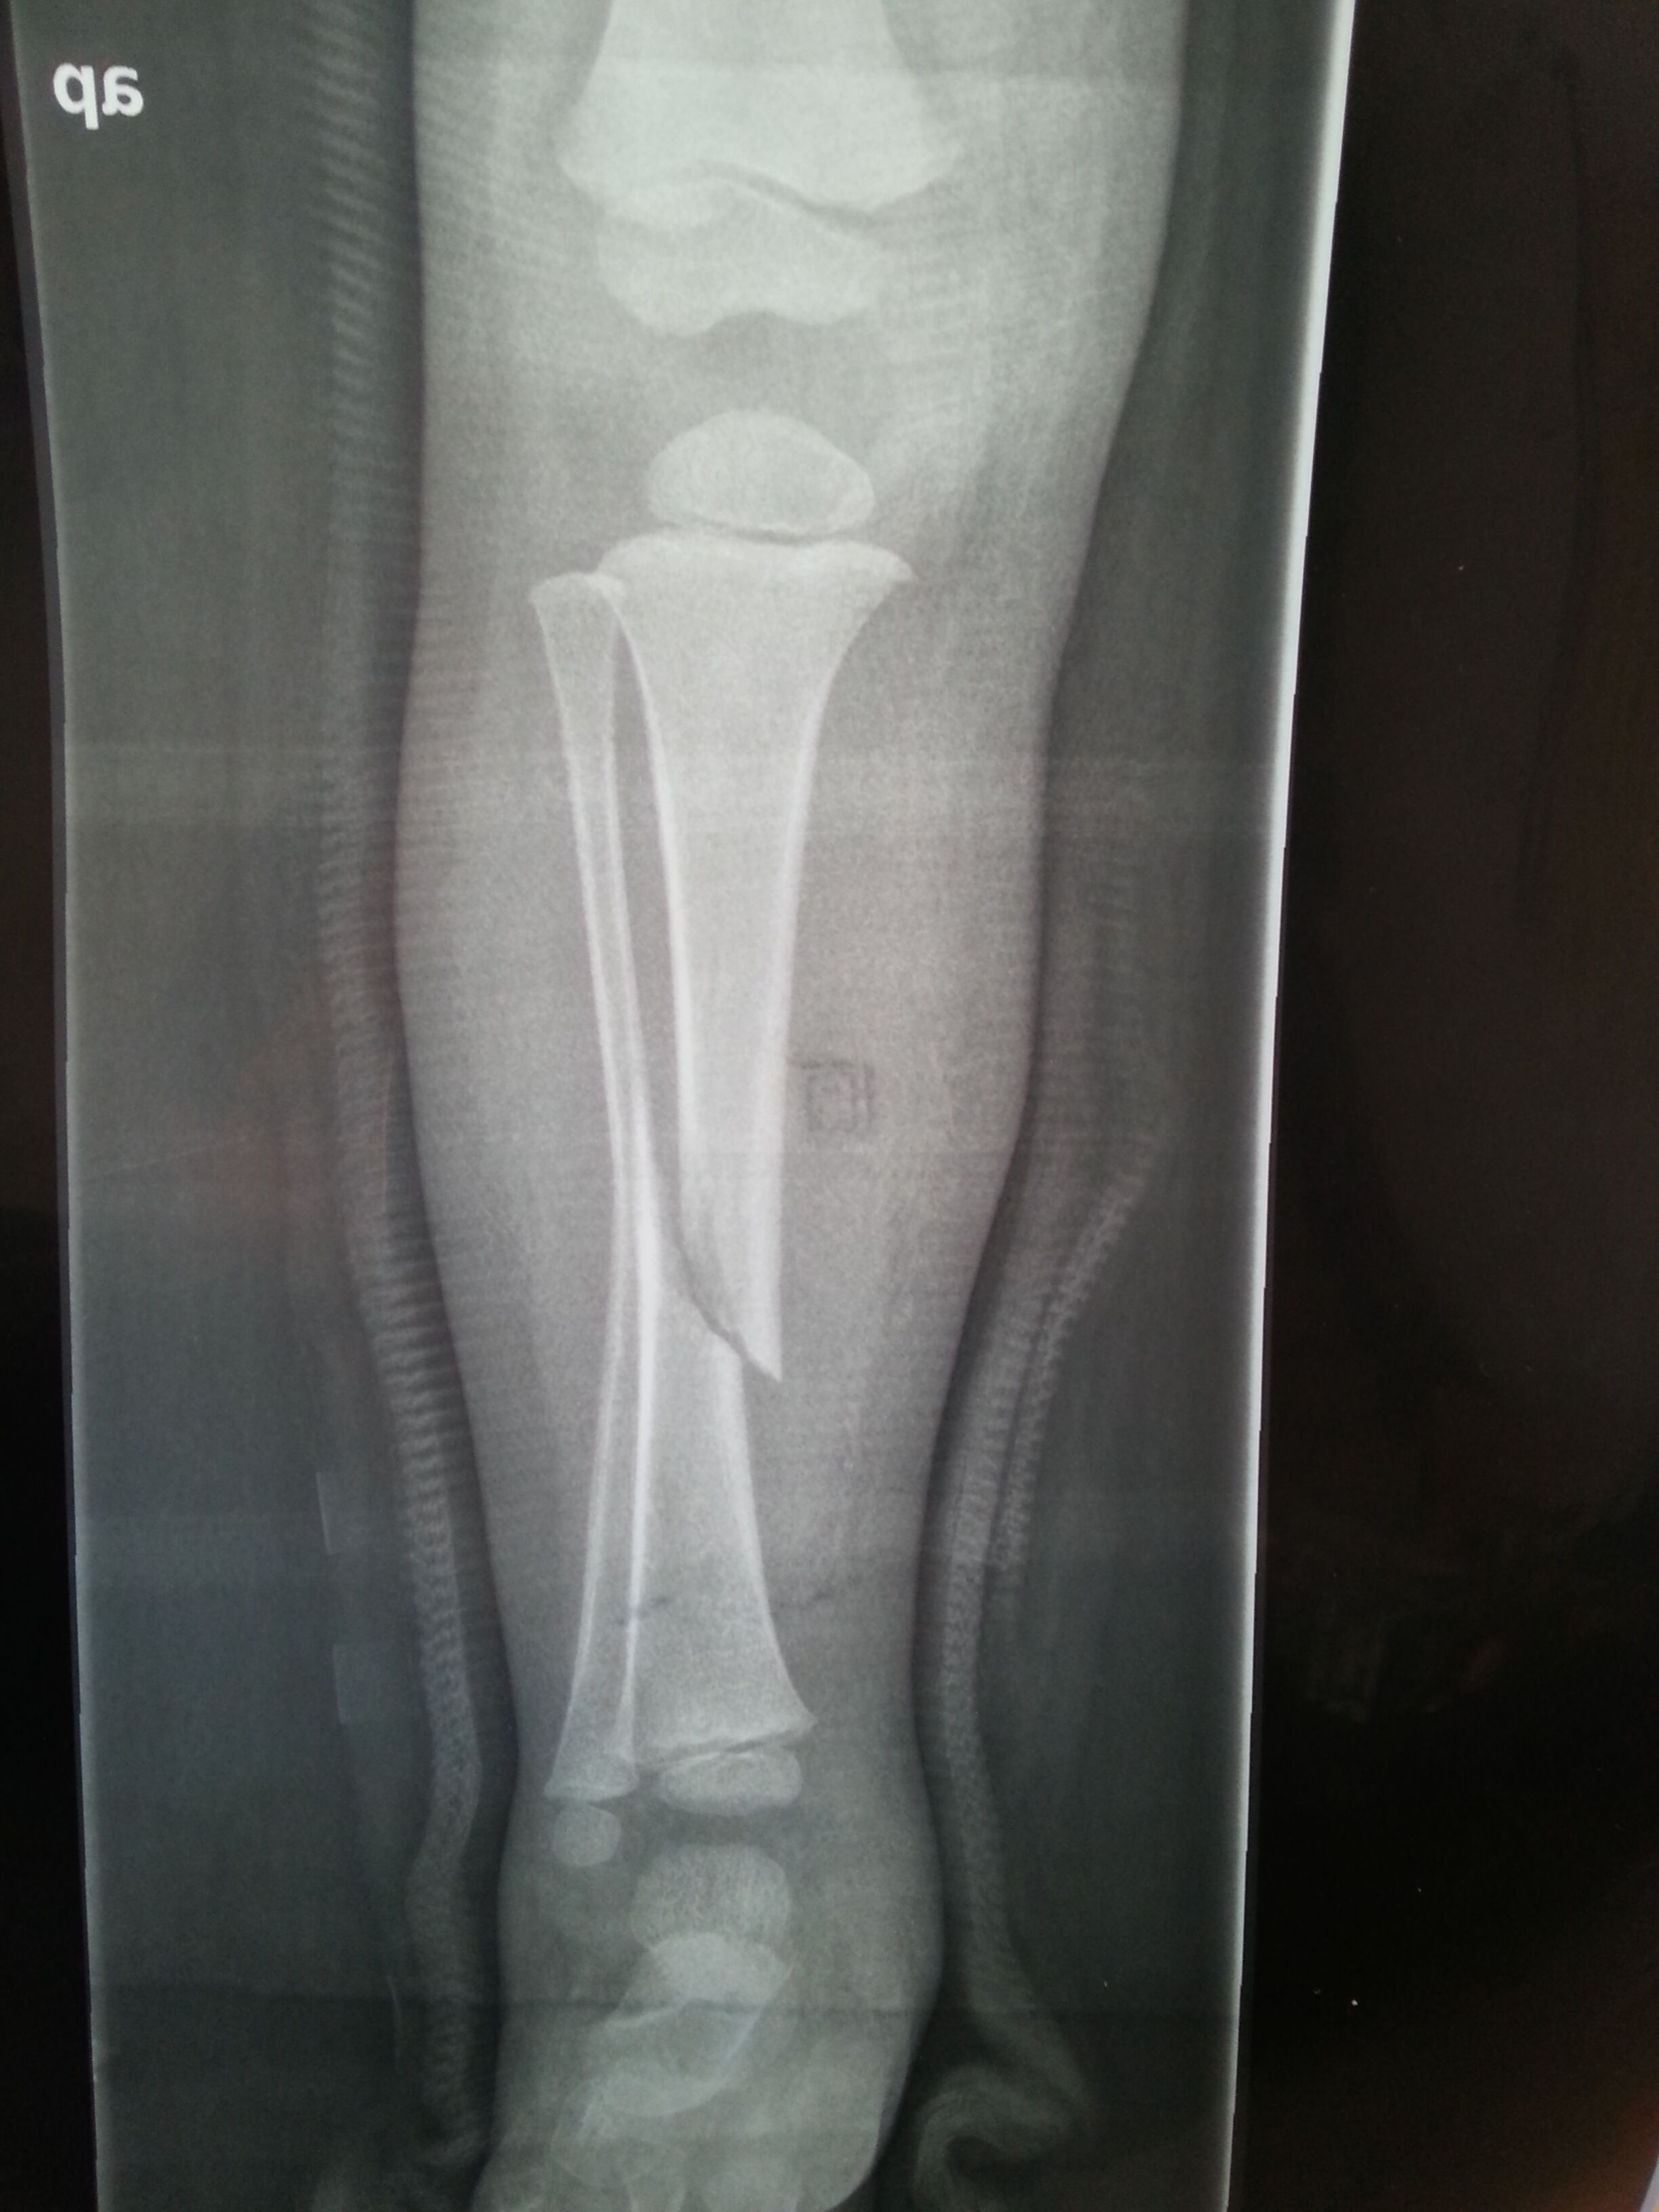

二岁五个月小孩小腿腓骨骨折这样可以长好吗?需要手术吗?怎么治疗比较好?走路会不会点腿?求专家 X片是事后二周拍的 点击展开 匿名用户 2015-03-06 15:49 为您推荐: 其他回答 你好 首先 你家孩子不是腓骨骨折,是胫骨骨折!!其次,这个骨折是斜形骨折,非稳定性骨折,所以错位很明显,而且中间还有蛮大的缝隙。这是需要手术的,如果就这么让他长,胫骨一个有可能长不好,还一个就是长好也是畸形的。建议手术治疗!! zhoubotong8046 2015-03-06 16:42 相关问题 小腿腓骨骨折五个月了还不能走路,这是正常的吗? 小腿左胫腓骨骨折,需要多长时间能走路? 小腿胫腓骨骨折多久能走路啊